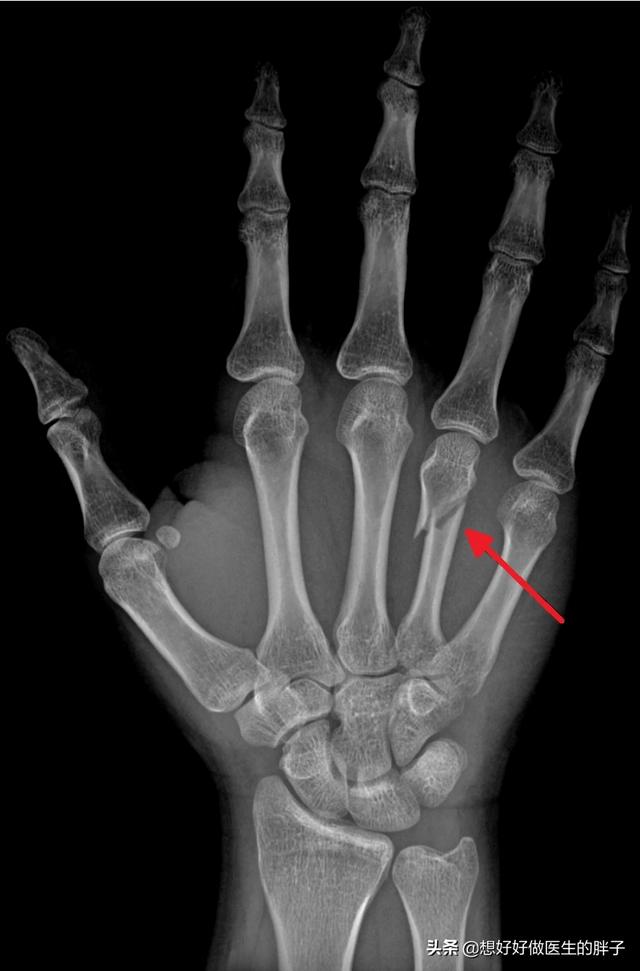

左侧第4掌骨骨折

左手第四掌骨斜性骨折